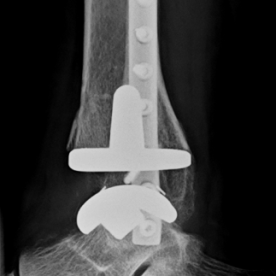

Röntgenbilder